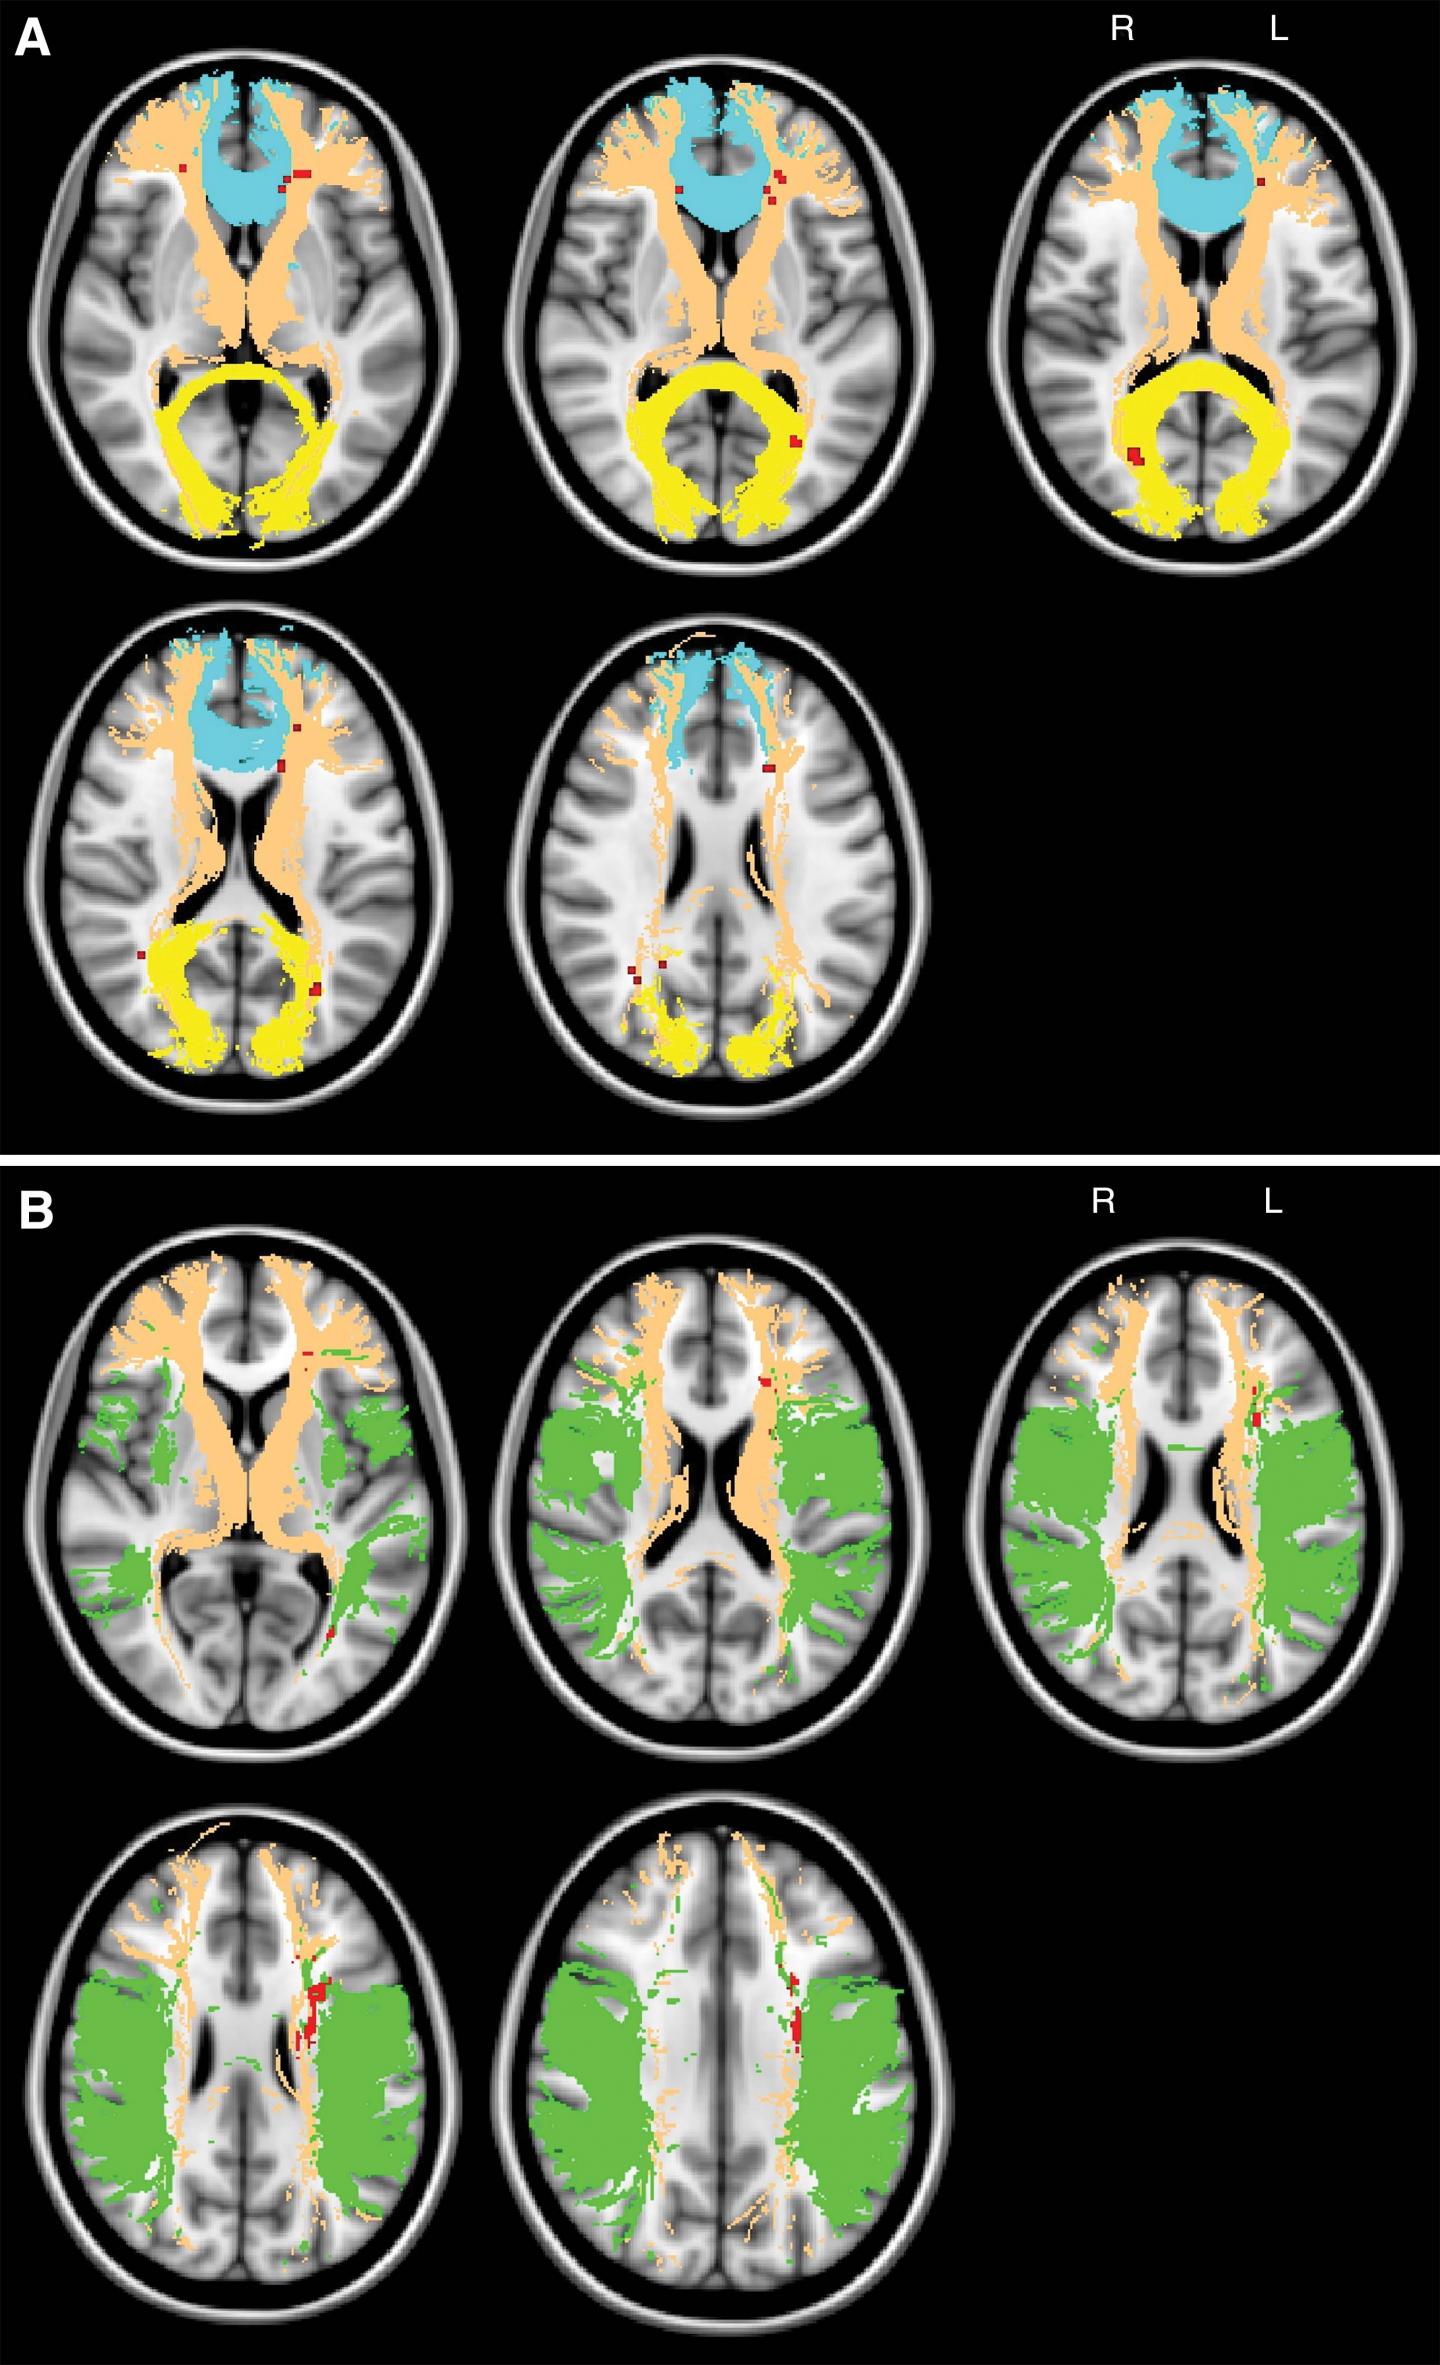

A biomarker that could predict and track vascular cognitive disorder on imaging exams has yet to be found, although MRI measurements of the brain's signal-carrying white matter are a promising area of research. Damage to the white matter can be assessed with diffusion tensor imaging, an MRI technique that provides two important measures of microscopic brain damage: mean diffusivity and fractional anisotropy. Increased mean diffusivity, which measures the movement of water through tissue, is particularly sensitive to the breakdown of nerve fibers in the brain and the protective coating around them.

For the new study, researchers assessed brain MRI and cognitive examination results from 108 patients with symptomatic carotid artery disease, a risk factor for vascular cognitive disorder. Of the 108 patients, 53 were cognitively impaired. Further analysis showed a clear correlation between cognitive performance and the presence of chronic vascular disease-related lesions within certain white matter tracts of the brain. White matter tract skeleton mean diffusivity showed the closest correlation with impaired cognitive performance, making it a promising tool for improved diagnostic accuracy of vascular cognitive disorder.

"Using standard clinical brain MRI, we found that microscopic damage of main white matter tracts allowed us to distinguish patients with symptomatic carotid artery disease and cognitive impairment from those who were cognitively intact," said the study's senior author, Dorothee P. Auer, Ph.D., from the University of Nottingham. "Our findings mean that a simple MRI test might improve the diagnostic work-up of people with suspected vascular cognitive disorder, and holds further promise to track progression of the disorder."

The results suggest that a key mechanism of vascular cognitive disorder is subcortical disconnection, a kind of breakdown of communication within the large-scale cognitive neural networks.

Dr. Auer explained that the brain is functionally organized into networks that require efficient communication across specific brain regions. This communication depends on the information flow between the network nodes, not unlike the flow of passenger traffic through an extensive urban subway system. Subcortical disconnection suggests a disruption in connections between such cognitive nodes, impairing information flow and thus network coordination.